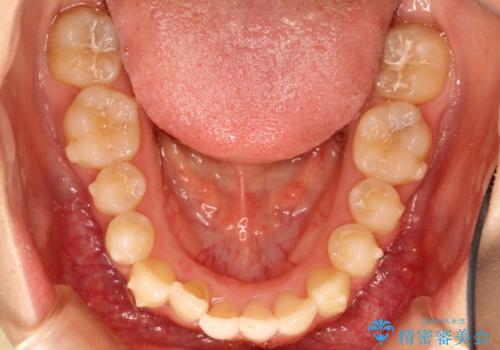

初診時の歯並びの状態としては、上下ともに全体に及ぶの中等度以上のがたつき(叢生)があり、前歯数本が反対交合の状態でした。

強い叢生がありましたが、抜歯は行わず上下顎ともに、主に歯列弓の拡大とディスキング(歯と歯の間に隙間を作る処置)を行い叢生を改善しました。